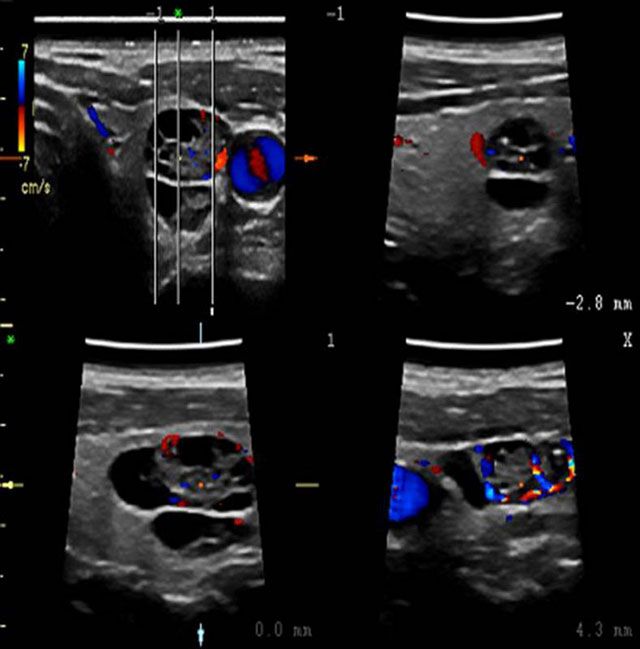

Η τεχνολογία Matrix που ενσωματώνεται στην ηχοβόλο κεφαλή M12L επιτυγχάνει εστίαση και επεξεργασία της υπερηχογραφικής εικόνας σε τρεις διαστάσεις, για υψηλή ακρίβεια τομής, ευκρίνεια και ποιότητα εικόνας στις εξετάσεις μαστού, θυρεοειδούς και λοιπών επιφανειακών οργάνων.

Με τη χρήση της κεφαλής αυτής επιτυγχάνεται ο εντοπισμός και διάγνωση μικρών όγκων, καθώς και η ανίχνευση ανώμαλων νεόπλαστων αγγειακών δομών. Ενσωματώνει τη μοναδική επαναστατική πλατφόρμα υπερηχοτομογραφίας Truscan, η οποία καθιστά δυνατή την αποθήκευση των αυθεντικών ακουστικών δεδομένων (digital raw data) για πλήρη και πραγματική μεθ’ επεξεργασία των διενεργούμενων εξετάσεων, ώστε να δίδεται η δυνατότητα στον ιατρό να μελετά διεξοδικά τις υπερηχογραφικές εικόνες σε δεύτερο χρόνο, χωρίς να επιβαρύνεται και να ταλαιπωρείται ο ασθενής.